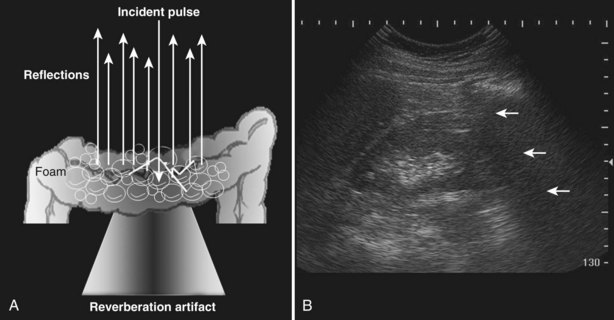

A reverberation artifact results when there are large differences in impedance between two adjacent tissues or surfaces with a strong reflection of the incident wave. The ultrasound wave bounces back and forth (reverberates) between the transducer interface and the reflective interface. With the second transit of the sound wave, the ultrasound equipment interprets a second object that is twice as far away as the first. There is ongoing attenuation of the sound wave with each successive reverberation, resulting in a slightly less intense image displayed on the screen. Therefore echoes are produced, spaced at equal intervals from the transducer but progressively less intense (Fig. 4–25).

Figure 4–25 Reverberation artifact: The strongly reflective interface is projected with decreasing amplitude as the incident sound wave makes multiple round trips.

The reverberation artifact can also be seen in cases where the incident sound wave strikes a series of smaller reflective objects (such as the gas-fluid mixture in the small bowel), which results in multiple reflected sound waves of various angles and intensity (Fig. 4–26). The resultant echo pattern is a collection of hyperechoic artifactual reflections distal to the structure with progressive attenuation of the sound wave.